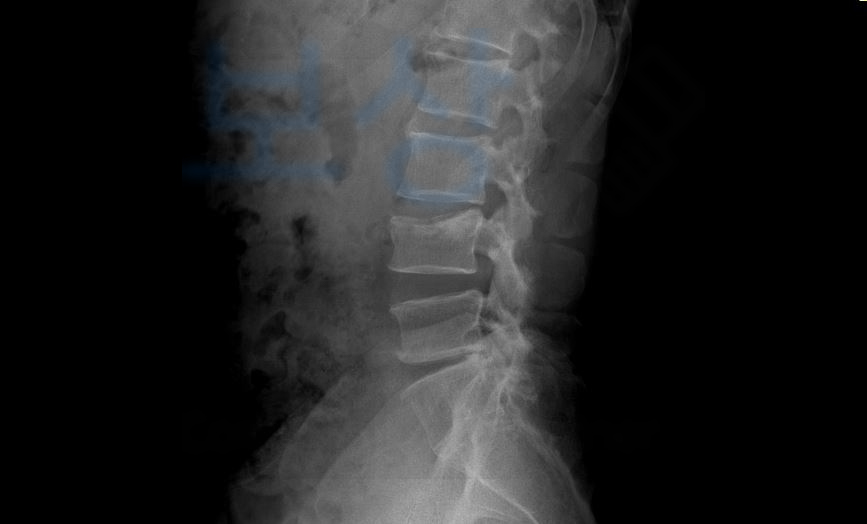

오늘 소개해 드릴 허@@님은 계단에서 미끄러지는 사고를 당하셔서 요추 골절 S32040 진단을 받게 되셨습니다.

진단서를 보시는 것처럼 허리보조기 TLSO를 착용하시면서 전치 6주 진단을 받으셨습니다. 6주의 시간이 경과하자 허리통증이 약간씩 나아지는 것을 느끼셨는데요, 가능할 수 있습니다. 여러분들이 개인적으로 가입하신 보험증권을 보시면

항목이 있으신가요? 보험 약관을 펼쳐 보시면 수술을 안한 척추여도 심한, 뚜렷한, 약간의 기형에 따라 후유장해 보험금 청구가 가능합니다. 허@@님은 사고 초기부터 보상파트너를 만나 영상CD와 보험 증권을 분석하여 상담을 도와드렸고 보험금 청구를 위임해주셔서 함께 진행하게 되었습니다.